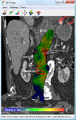

Biomechanical AAA rupture risk prediction

An axial contrast enhanced CT scan demonstrating an abdominal aortic aneurysm of 4.8 by 3.8 cm